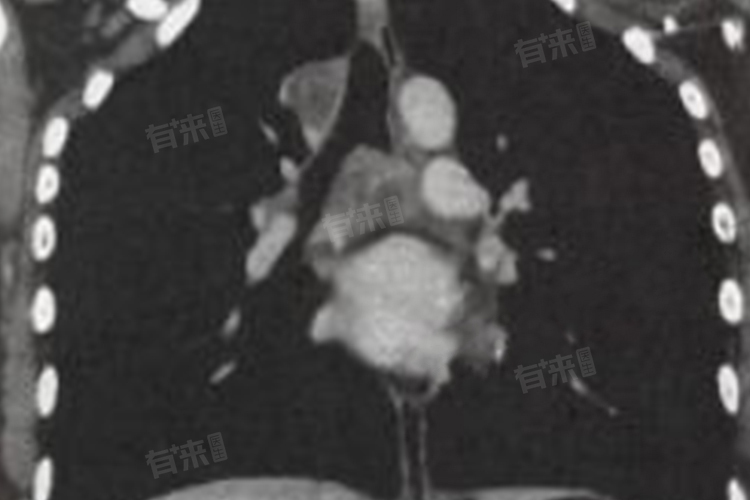

肺结核在胸片上有多种典型表现,原发性肺结核在胸片上常呈现哑铃状双极征。这是因为结核菌初次侵入肺部后,在肺内形成原发病灶,同时结核菌沿淋巴管蔓延至肺门淋巴结,原发病灶、淋巴管炎和肺门淋巴结肿大共同构成哑铃状影像。原发病灶多位于上叶下部或下叶上部近胸膜处,表现为边缘模糊的云雾状阴影,肺门淋巴结肿大则显示为肺门区域的结节状增大。